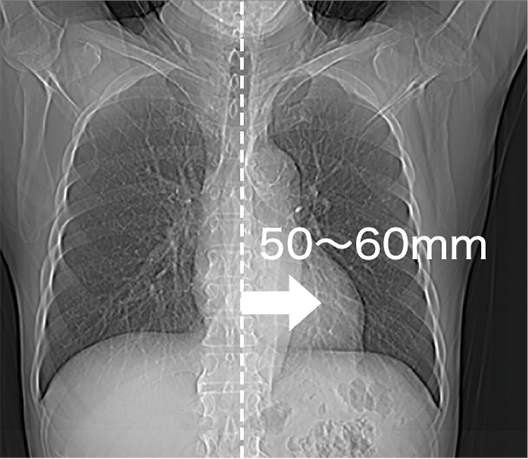

Stół pacjenta może przesuwać się poziomo do 200 mm, co ułatwia ustawienie zeskanowanego obszaru w środku, nawet obszarów serca lub ortopedycznych, takich jak bark. Oczekuje się, że poprawi to skuteczność badania.

Pozycjonowanie serca w środku pola obrazowania